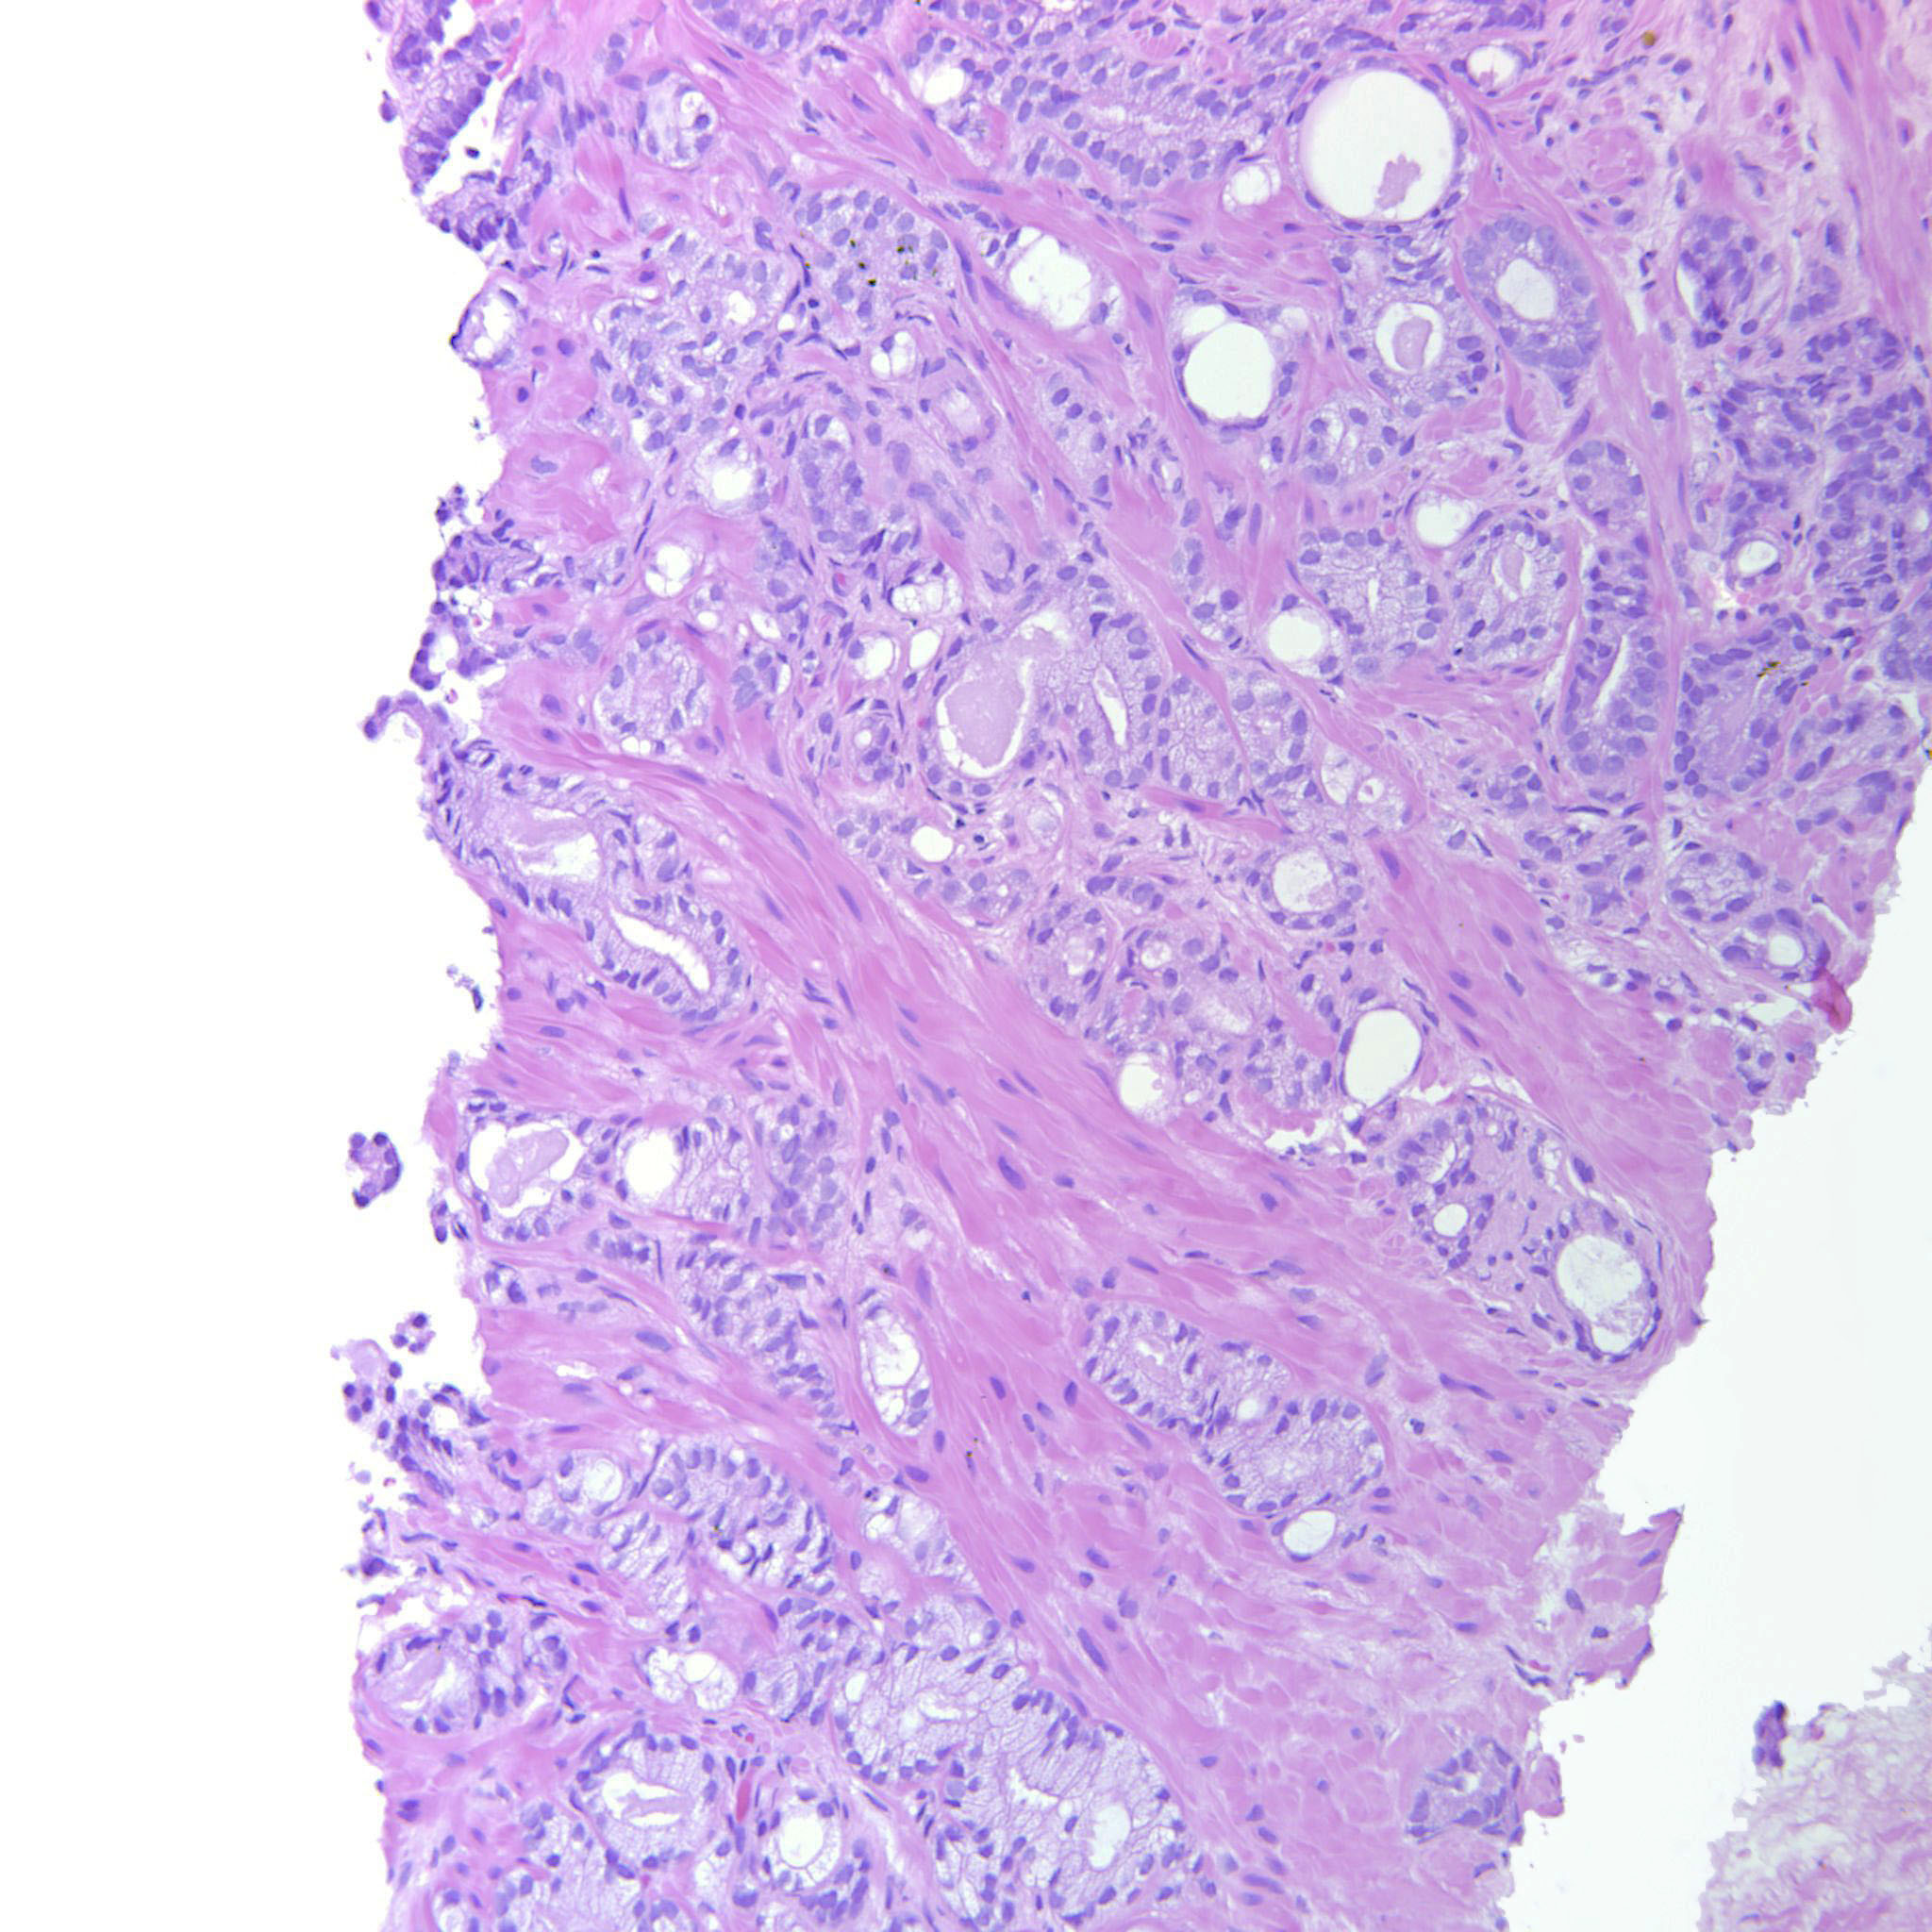

Consensus grade: GS 3+4=7 (ISUP 2)

Case description (by case creator):

Poorly formed and fused glands are seen.